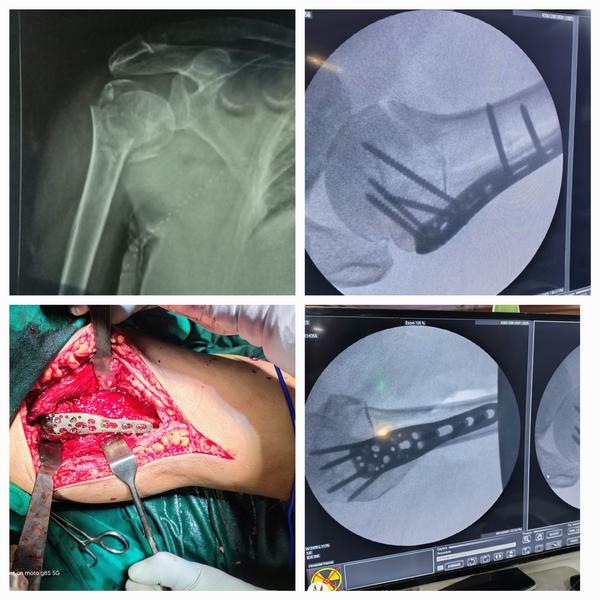

Fracture of Distal end Tibia and Fibula Fixation

Fracture of Distal end Tibia and Fibula Fixation.

READ MORESunshine Ortho Pain And Superspeciality Hospital is the Best Orthopedic Hospital in Wakad, Hinjewadi, PCMC and Pune. We are specialized in Orthopedic Surgeries, Robotic Joint Replacement Surgery, Hip and Knee Replacement Surgery, Complex Trauma And Pelvi Acetabular Surgery, Spine Surgery, Sports Medicine And Arthroscopy, Regenerative Therapy/Prolotherapy, Physiotherapy and Rahabilitation Center, Shoulder Surgery, Knee Surgeries, Foot And Ankle Treatment, Fracture Treatment in Wakad, Hinjewadi, PCMc and Pune.